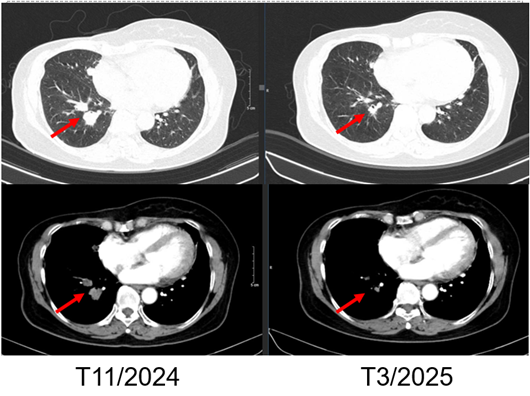

Hình 7. Hình ảnh chụp CT ngực trước và sau điều trị: Tổn thương tái phát thành ngực

Hình 8. Hình ảnh chụp CT ngực trước và sau điều trị: Tổn thương phổi trái

Hình 9. Hình ảnh chụp CT ngực trước và sau điều trị: Tổn thương phổi phải

– Chụp cắt lớp vi tính ngực:

+ Thành ngực phải có nốt đặc đường kính 5mm – theo dõi tổn thương tái phát

+ Phổi phải: nhu mô thuỳ giữa và dưới có các khối – nốt đặc, lớn nhất 7x8mm

+ Phổi trái: nhu mô thuỳ trên và đáy phổi sát màng phổi có các khối nốt đặc, lớn nhất 9x8mm

- Kết quả

Sau 3 chu kỳ điều trị với Palbociclib và Letrozole, bệnh nhân được đánh giá là đáp ứng một phần theo tiêu chuẩn RECIST. Các tổn thương trên lâm sàng và hình ảnh học đều giảm kích thước đáng kể, chất chỉ điểm khối u CA 15-3 giảm. Bệnh nhân dung nạp thuốc tốt, không ghi nhận độc tính đáng kể ngoài giảm bạch cầu trung tính độ 1, hiện không cần can thiệp gì.